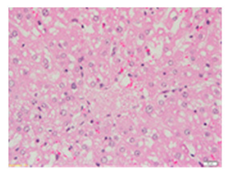

Liver wet weights of all rat groups showed no significant differences (Table 8). According to histochemical hematoxylin and eosin (H&E) staining, treatment with the highest dose of MPE (1000 mg/kg BW) did not result in morphological changes in the liver tissue (B) when compared with DI water treatment (A). Obviously, CCl4 induction (ip)/DI water treatment (po) caused hepatoxicity, which was indicated by a severe degree of fatty changes and fatty cysts in the liver tissue (C), whereas pretreatments of silymarin (100 mg/kg BW, po) effectively decreased the degree of fatty changes and fatty cysts in the liver when compared with the CCl4/DI water group. Indeed, MPE (250 and 1000 mg/kg BW, po) lowered the degree of lipid accumulation in the liver; inversely, MPE (500 mg/kg BW, po) exhibited a severe degree of lipid accumulation. Apparently, taking paracetamol (2 g/kg BW) induced a severe degree of hepatic necrosis when compared with rats that had not received the treatment. Similarly, pretreatments of silymarin (100 mg/kg BW, po) and MPE (250 and 1000 mg/kg BW, po) revealed a mild degree of hepatic necrosis, while MPE (500 mg/kg BW, po) revealed a moderate to severe degree of hepatic necrosis. Accordingly, the findings imply that the consumption of MPE (1000 mg/kg BW) was not harmful to the liver of healthy rats, while MPE (250 mg/kg BW) did improve fat deposition in the livers of CCl4-fed rats and offered protection against liver cell damage in paracetamol-fed rats.

Wet weight values (mean ± SD) and H&E staining of liver from rats with hepatotoxicity induced by CCl4 and paracetamol.